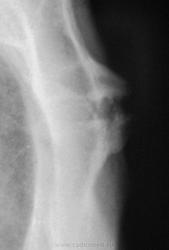

Снимки хорошие, но всё-таки сделал бы томографию. А так, скорее всего, признаки артроза в суставе между телом и рукояткой грудины.

Какой-то остеохондрит типа "Титце".

Артроз то - артрозом, но нет ли тут и асептического некроза нижне-внутреннего края рукоятки грудины....или мне секвестроподобная тень в этом участке "мерещится"?))))

Однако, при таких размеров "шишечке" клиника неблагополучия должна быть!